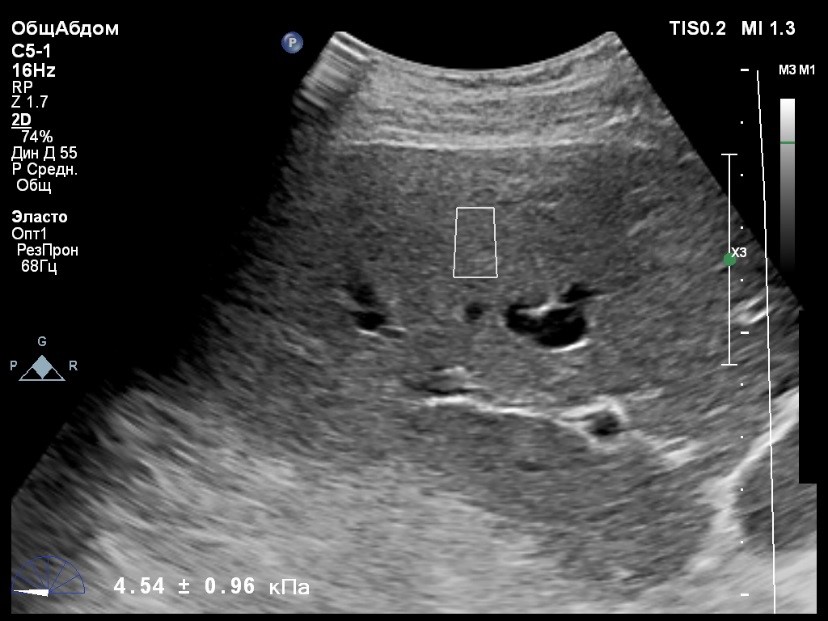

Пациент обратился к доктору с направлением на исследование степени жесткости печени в июне 2017 года. Из истории болезни, пациент страдает Гепатитом С с 2015 года. Лечение не получал. В апреле 2016 года, с помощью транзиентной эластографии была установлена медиана жесткости печени 5,8 kPA (4,4-7,7). На момент настоящего исследования, пациент не принимал пищу на протяжении 4 часов, АСТ, АЛТ не превышают патологических значений. Для оценки жесткости была выбрана технология компании Philips ElastPQ (точечная эластография) и прибор компании Philips Epiq 7 Исследование было проведено в соответствии с клиническими рекомендациями для ультразвуковых приборов компании Philips. В результате исследования были получены следующие результаты:

| 1 [4.94] kPa | 2 [7.09] kPa | 3 [7.13] kPa |

| 4 [4.74] kPa | 5 [5.17] kPa | 6 [7.78] kPa |

| 7 [6.19] kPa | 8 [7.63] kPa | 9 [4.64] kPa |

| 10 [6.18] kPa | 11 [4.49] kPa | 12 [4.54] kPa |

| 13 [6.08] kPa | | |

Стандартное Отклонение [1.17] kPa Медиана Жесткости [6.08] kPa Фактор Качества IQR/Med 9%

Зона интереса расположена на более чем на один сантиметр глубже капсулы, параллельно ходу луча, в середине изображения, в участке печени лишенном артефактов.

Капсула видна как белая линия перпендикулярная ходу ультразвукового луча, исследования производятся приблизительно в одном и том же сегменте печени.

Стандартное отклонение (0,96 kPA) не превышает 30 процентов от полученного значения (4,54 kPA).

Зона интереса расположена вне крупных сосудов.

Для интерпретации полученных клинических данных были использованы Рекомендации по проведению эластографии сдвиговой волной для оценки жесткости печени при использовании ультразвуковых аппаратов компании Филипс с примером протокола. Анамнез основного заболевания пациента достаточно короткий и показатели жесткости печени, полученные в 2016 свидетельствуют об отсутствии значимых фиброзных изменений. Однако, в течении всего времени пациент не получал специфического лечения. Данный факт является показанием для динамического наблюдения и оценки жесткости печени. Подготовка пациента соответствовала проводимому исследованию. Представленные слайды проведенного исследования свидетельствуют о правильном техническом исполнении проб, что позволяет заключиться о достоверности полученных измерений. Таким образом, учитывая полученную медиану жесткости на уровне 6.08 кРа (4.49 – 7.78 kPa) и уровень стандартных отклонений не превышающих 30%, полагаю, что уровень степени фиброза соответствует стадии F 0-1. Заведующий отделением УЗД МЦ «Асклепий», Глушенко Д. Е.